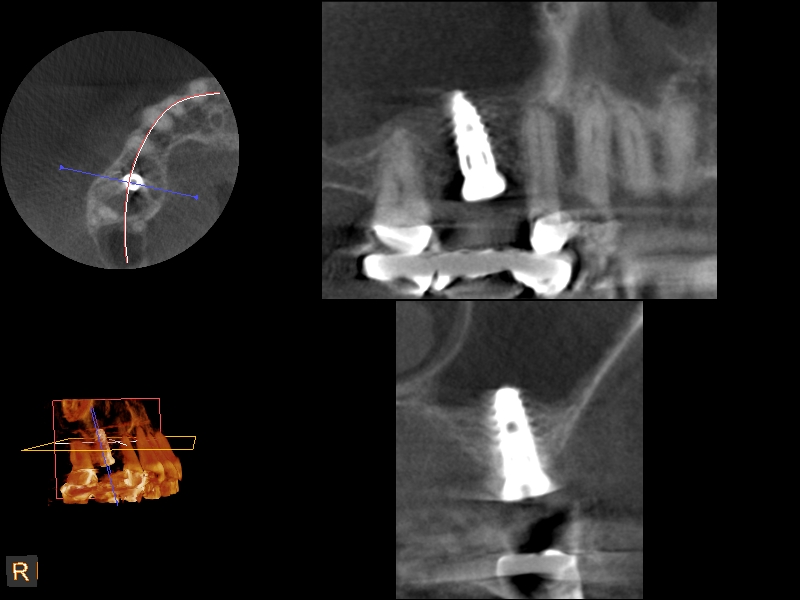

A 4-month CBCT scan (Kodak 9000D) of

implant No. 14.

Fig. 7

Because the bone grafting materials used in this technique need physical stability during healing to support the raised membrane, there is a high probability that significant shrinkage of the graft will occur as it heals and matures if only non-demineralized material is used. For these reasons, a composite graft using calcium sulfate, DFDBA, and mineralized particulate bone is used. A 50:50 mixture by volume of mineralized bone grafting material and DFDBA is used, to which approximately 40% calcium sulfate by volume is added. A higher percentage of calcium sulfate is used relative to that described for composite grafting in other uses, because some of the calcium sulfate will wash out during bone packing. Another advantage to this composite graft is that it is not as radiopaque as a purely mineralized graft. This allows radiographic monitoring of the bone healing around the implant, which can be used to time abutment placement on the implant. This is demonstrated in Figure 4 and Figure 5, which are radiographs taken on the day of the initial surgery showing the radiographic appearance of the composite graft, implant, and graft, and in Figure 6, a 5-month postoperative radiograph with the abutment in place. The old floor of the sinus is indistinguishable from the area of new bone. Figure 7 shows a CBCT scan (Carestream Dental, www.carestreamdental.com) taken at 4 months with the old floor of the sinus indistinguishable from the new bone formed.

The implant is then delivered and should be well stabilized in the bone. If there is any mobility of the implant, it can either be placed a little deeper (if there is enough native bone) or the implant can be removed and the procedure aborted, in which case it would be a two-stage procedure. This should rarely occur with the tapered designed implant, even with only 2 mm of native bone. Using a bone-level platform-shifting implant (or a tissue-level designed implant) is critical, as the hard and soft tissue will establish a biologic width. If an external hex type of implant is used and the shoulder is placed at the bone level, an expected bone loss of 1.5 mm to 2 mm will occur.24 Figure 10 shows proper bone-level implant depth placement with a platform-shifting design. In this case, a 3-mm healing abutment was placed at the time of surgery to avoid a secondary uncovering surgery, but an implant-level healing abutment could have been placed instead. As can be seen, there was only about 2 mm to 3 mm of native bone height. The membrane was raised about 8 mm to 9 mm. Comparing the radiograph on the day of surgery (Figure 10) to the 6-month postoperative radiograph (Figure 11) shows no loss of native bone, as well as the positive change in appearance of the grafted bone. The 3.5-month CBCT scan (Figure 12) shows good healing of the bone with no coronal bone loss. With minimal native bone present, as in this case, the use of a non-platform-shifting or non-tissue-level implant design could be problematic. After 1.5 mm to 2 mm of crestal bone loss, an external hex designed implant could develop instability with possible implant failure. If a non-tapered implant is used and bone loss occurs during healing, migration of the implant into the sinus could potentially occur. The surgeon can use either a healing abutment or implant-level closure screw over the implant shoulder. With patients who tend to use their tongues to explore or play with the area, or if the area is under a removable partial denture, a closure screw is recommended.